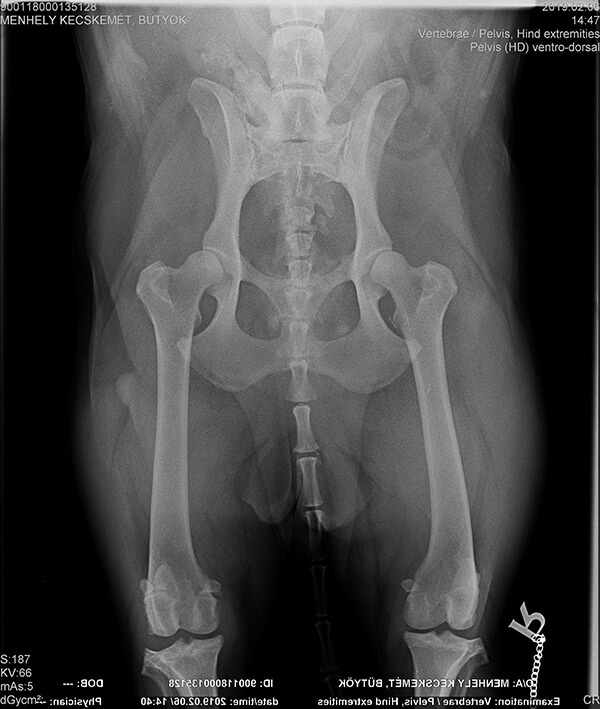

Zu allem Unglück leidet Bütyök an einem alten Kreuzbandriss und Arthrose im Knie. Das Kreuzband wird am 21.2.19 in Budapest operiert.